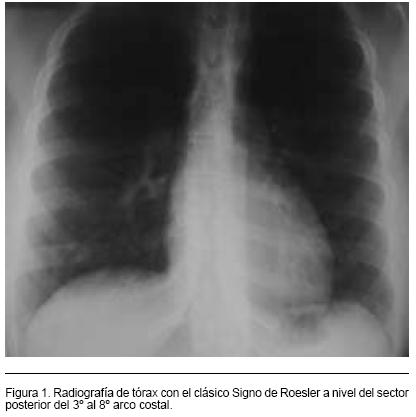

Radiografía de Tórax: silueta cardio-pericárdica donde se destaca un ápex redondeado como elemento de HVI. Franca aortomegalia. Erosiones costales evidentes en arcos posteriores de la tercera a octava costillas (Signo de Roesler) (Figura 1)

Desde el punto de vista paraclínico la Rx.Tx. y el ECG frecuentemente presentan alteraciones, aunque ninguna de ellas es patognomónica de la enfermedad. En la Rx.Tx. Es típico el hallazgo de muescas costales (signo de Roesler) secundarias a la erosión producida por las arterias intercostales dilatadas (que funcionan como circulación colateral). En el ECG se puede observar en los casos severos elementos de HVI, sobrecarga sistólica ventricular izquierda, y bloqueo completo de rama izquierda. El Ecocardiograma transtorácico doppler color es el método diagnóstico fundamental para la detección de la coartación de aorta, permitiendo su visualización, la valoración de su repercusión anatómica y funcional sobre las cavidades cardíacas, y la asociación con otras malformaciones intracardíacas. Mediante el doppler es posible determinar su severidad a través de la medición del gradiente de presiones entre la aorta proximal y distal a la coartación.(3,5)